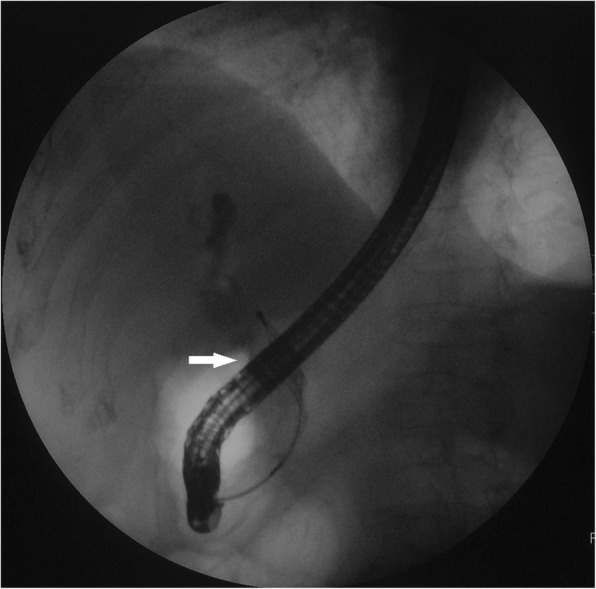

A high-density image of the middle CBD with a markedly dilated biliary tree was revealed on the second CT (Fig. 3). Thus, ERCP was repeated. A long filling defect was noted in the dilated common bile duct (Fig. 4), and a blood clot (maximum diameter 35 mm × 10 mm) was extracted with a basket (Fig. 5). Then, an endoscopic nasobiliary drainage (ENBD) tube was inserted into the CBD to ensure continued biliary drainage. Two days later, her temperature returned to normal, and abdominal pain was relieved. Histopathological examination revealed massive red blood cells with white blood cells and tissue necrosis (Fig. 6). After the treatment, she recovered and was discharged without any other complication.